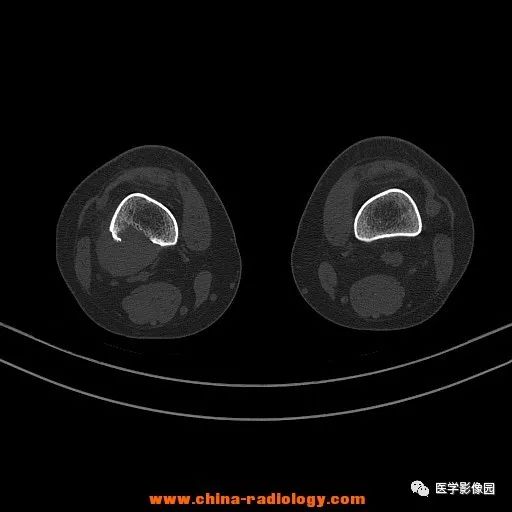

患者女性,29岁,右膝关节痛疼3月余,局部无红肿。

影像学表现:右股骨远端外后方可见局限性骨质破坏及软组织肿块,边界清楚。